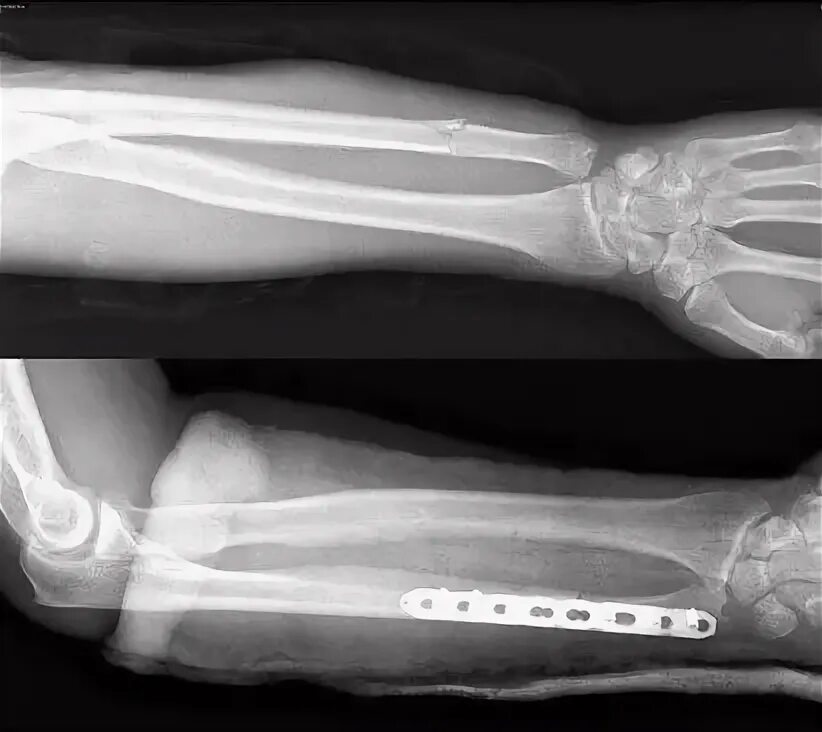

Остеосинтез перелома лучевой кости. перелом костей предплечья рентген. остеосинтез лучевой кости рентген. перелом диафиза лучевой кости рентген.

Остеосинтез перелома лучевой кости. перелом локтевого отростка локтевого сустава. переломы локтевого отростка вебер. перелом локтевой кости рентген.

Остеосинтез лучевой кости. переломы локтевого отростка остеосинтез винтом. остеосинтез акс пластиной. остеосинтез переломов локтевой кости.